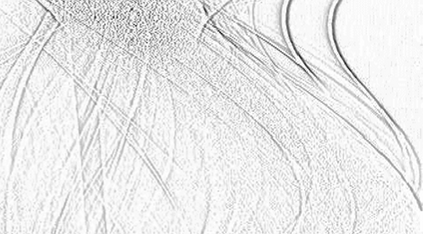

Low-Dose Computed Tomography (LDCT) technique, which reduces the radiation harm to human bodies, is now attracting increasing interest in the medical imaging field. As the image quality is degraded by low dose radiation, LDCT exams require specialized reconstruction methods or denoising algorithms. However, most of the recent effective methods overlook the inner-structure of the original projection data (sinogram) which limits their denoising ability. The inner-structure of the sinogram represents special characteristics of the data in the sinogram domain. By maintaining this structure while denoising, the noise can be obviously restrained. Therefore, we propose an LDCT denoising network namely Sinogram Inner-Structure Transformer (SIST) to reduce the noise by utilizing the inner-structure in the sinogram domain. Specifically, we study the CT imaging mechanism and statistical characteristics of sinogram to design the sinogram inner-structure loss including the global and local inner-structure for restoring high-quality CT images. Besides, we propose a sinogram transformer module to better extract sinogram features. The transformer architecture using a self-attention mechanism can exploit interrelations between projections of different view angles, which achieves an outstanding performance in sinogram denoising. Furthermore, in order to improve the performance in the image domain, we propose the image reconstruction module to complementarily denoise both in the sinogram and image domain.